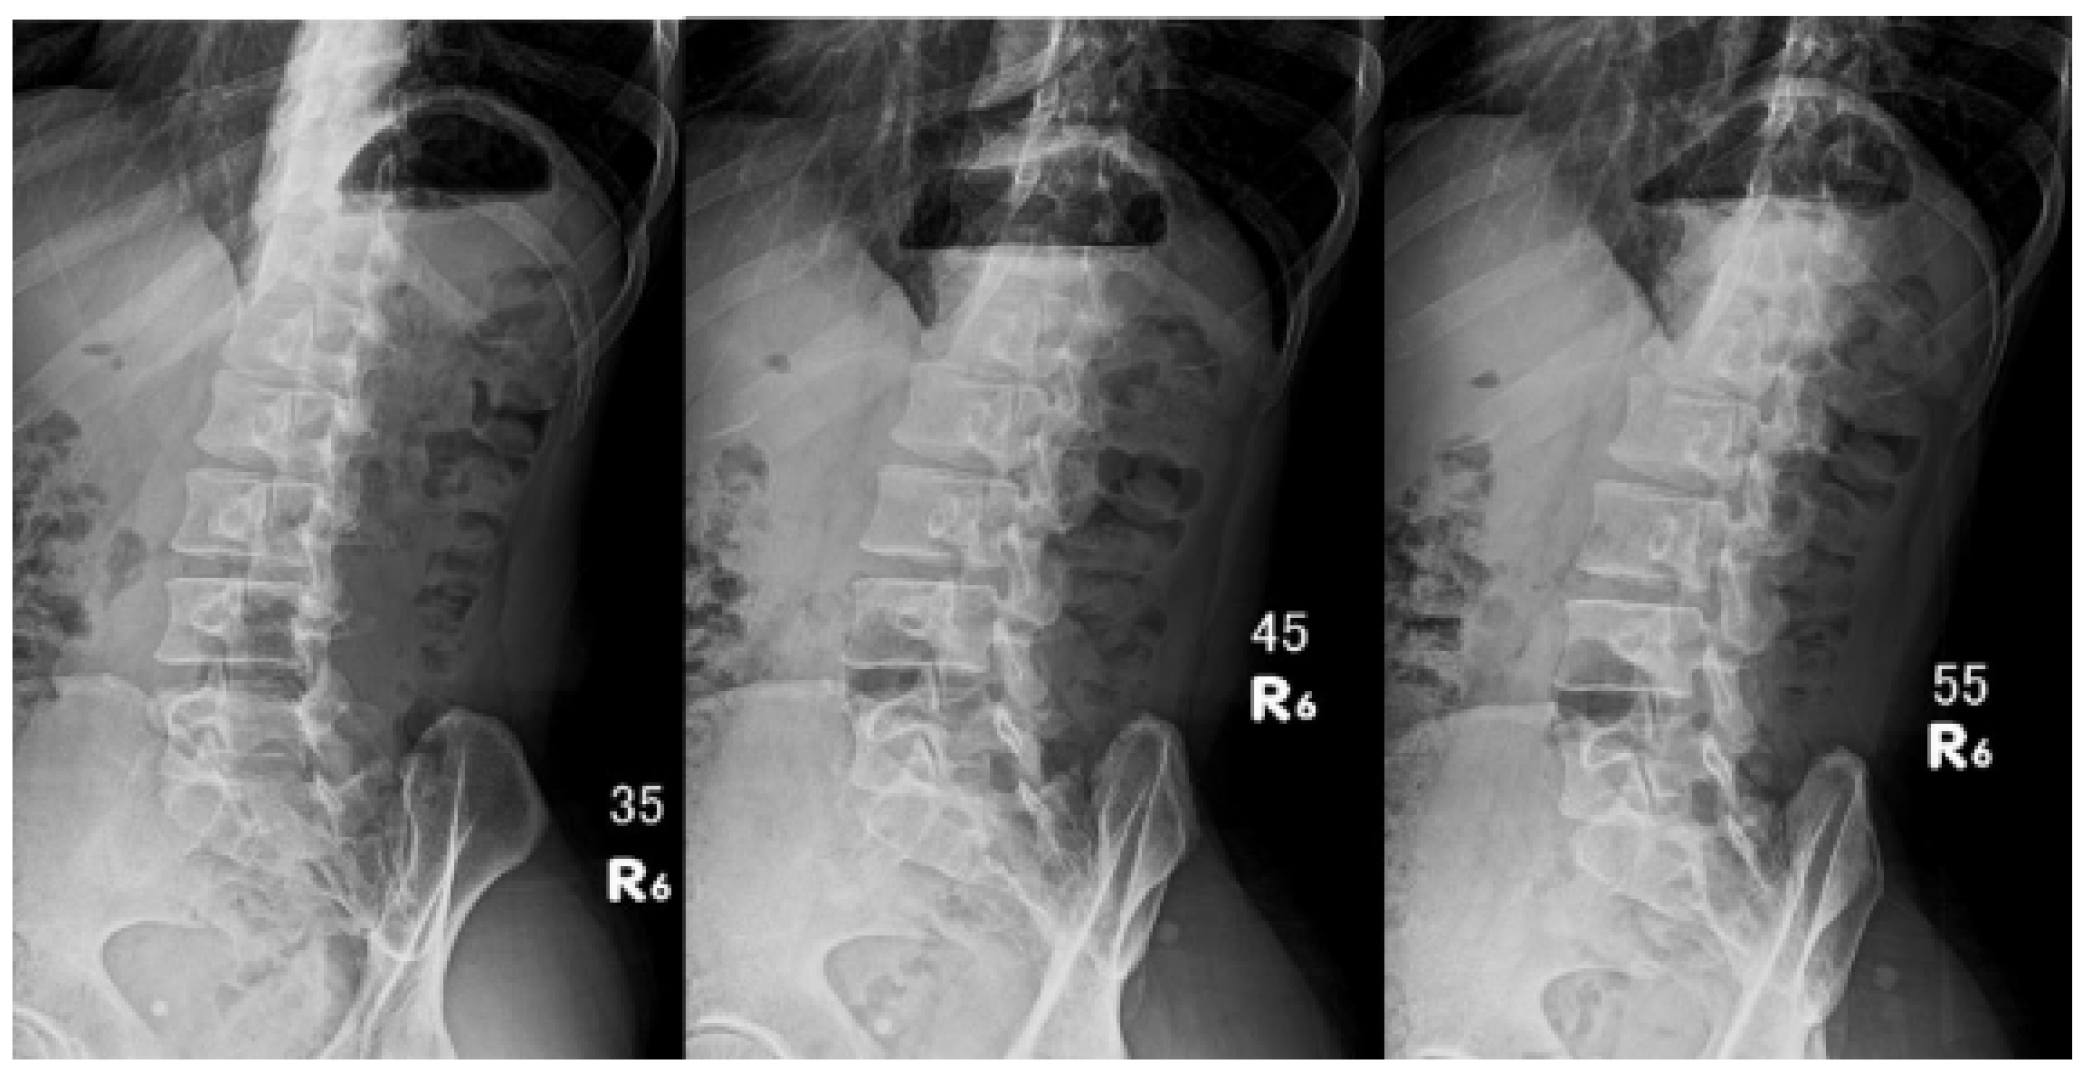

Evaluation of Optimized Lumbar Oblique X-Ray Angles with Positioning Assistance for Enhanced Imaging Quality: A Pilot Study in an Asian Cohort

3. Results